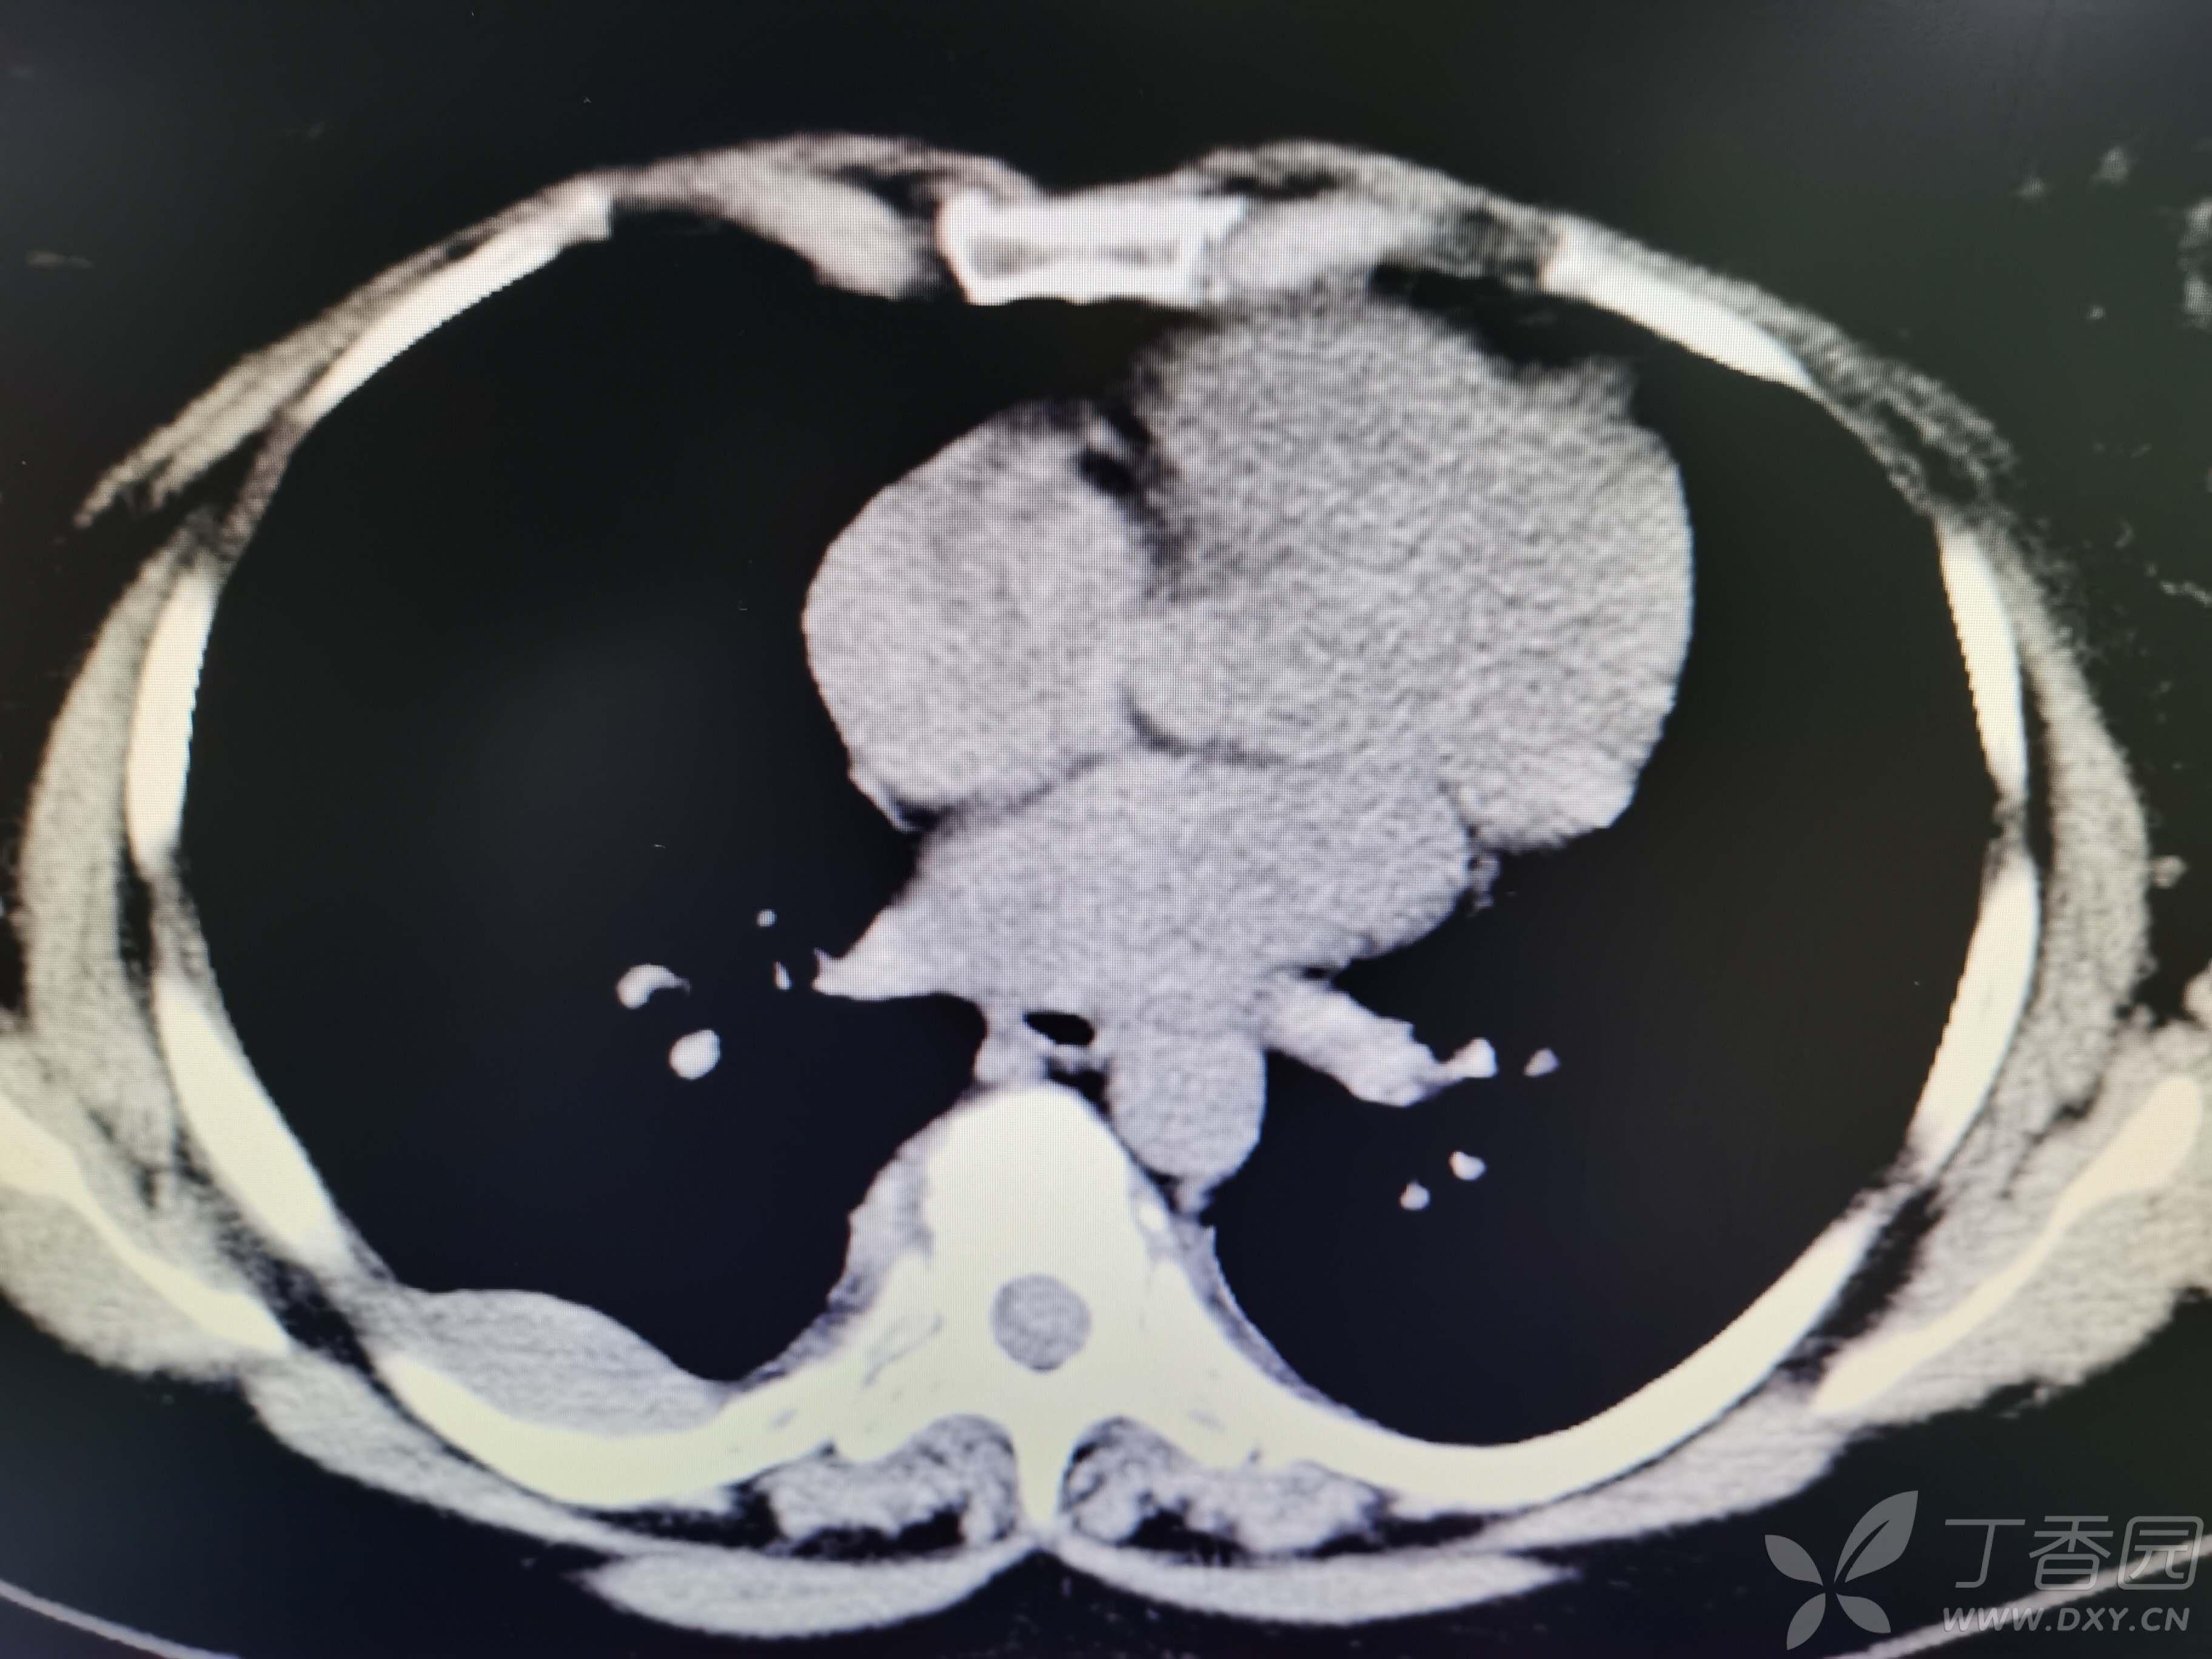

基本信息:女,三十几岁,印度人。。

胸部CT:

如题:猜肺部病灶病理。。